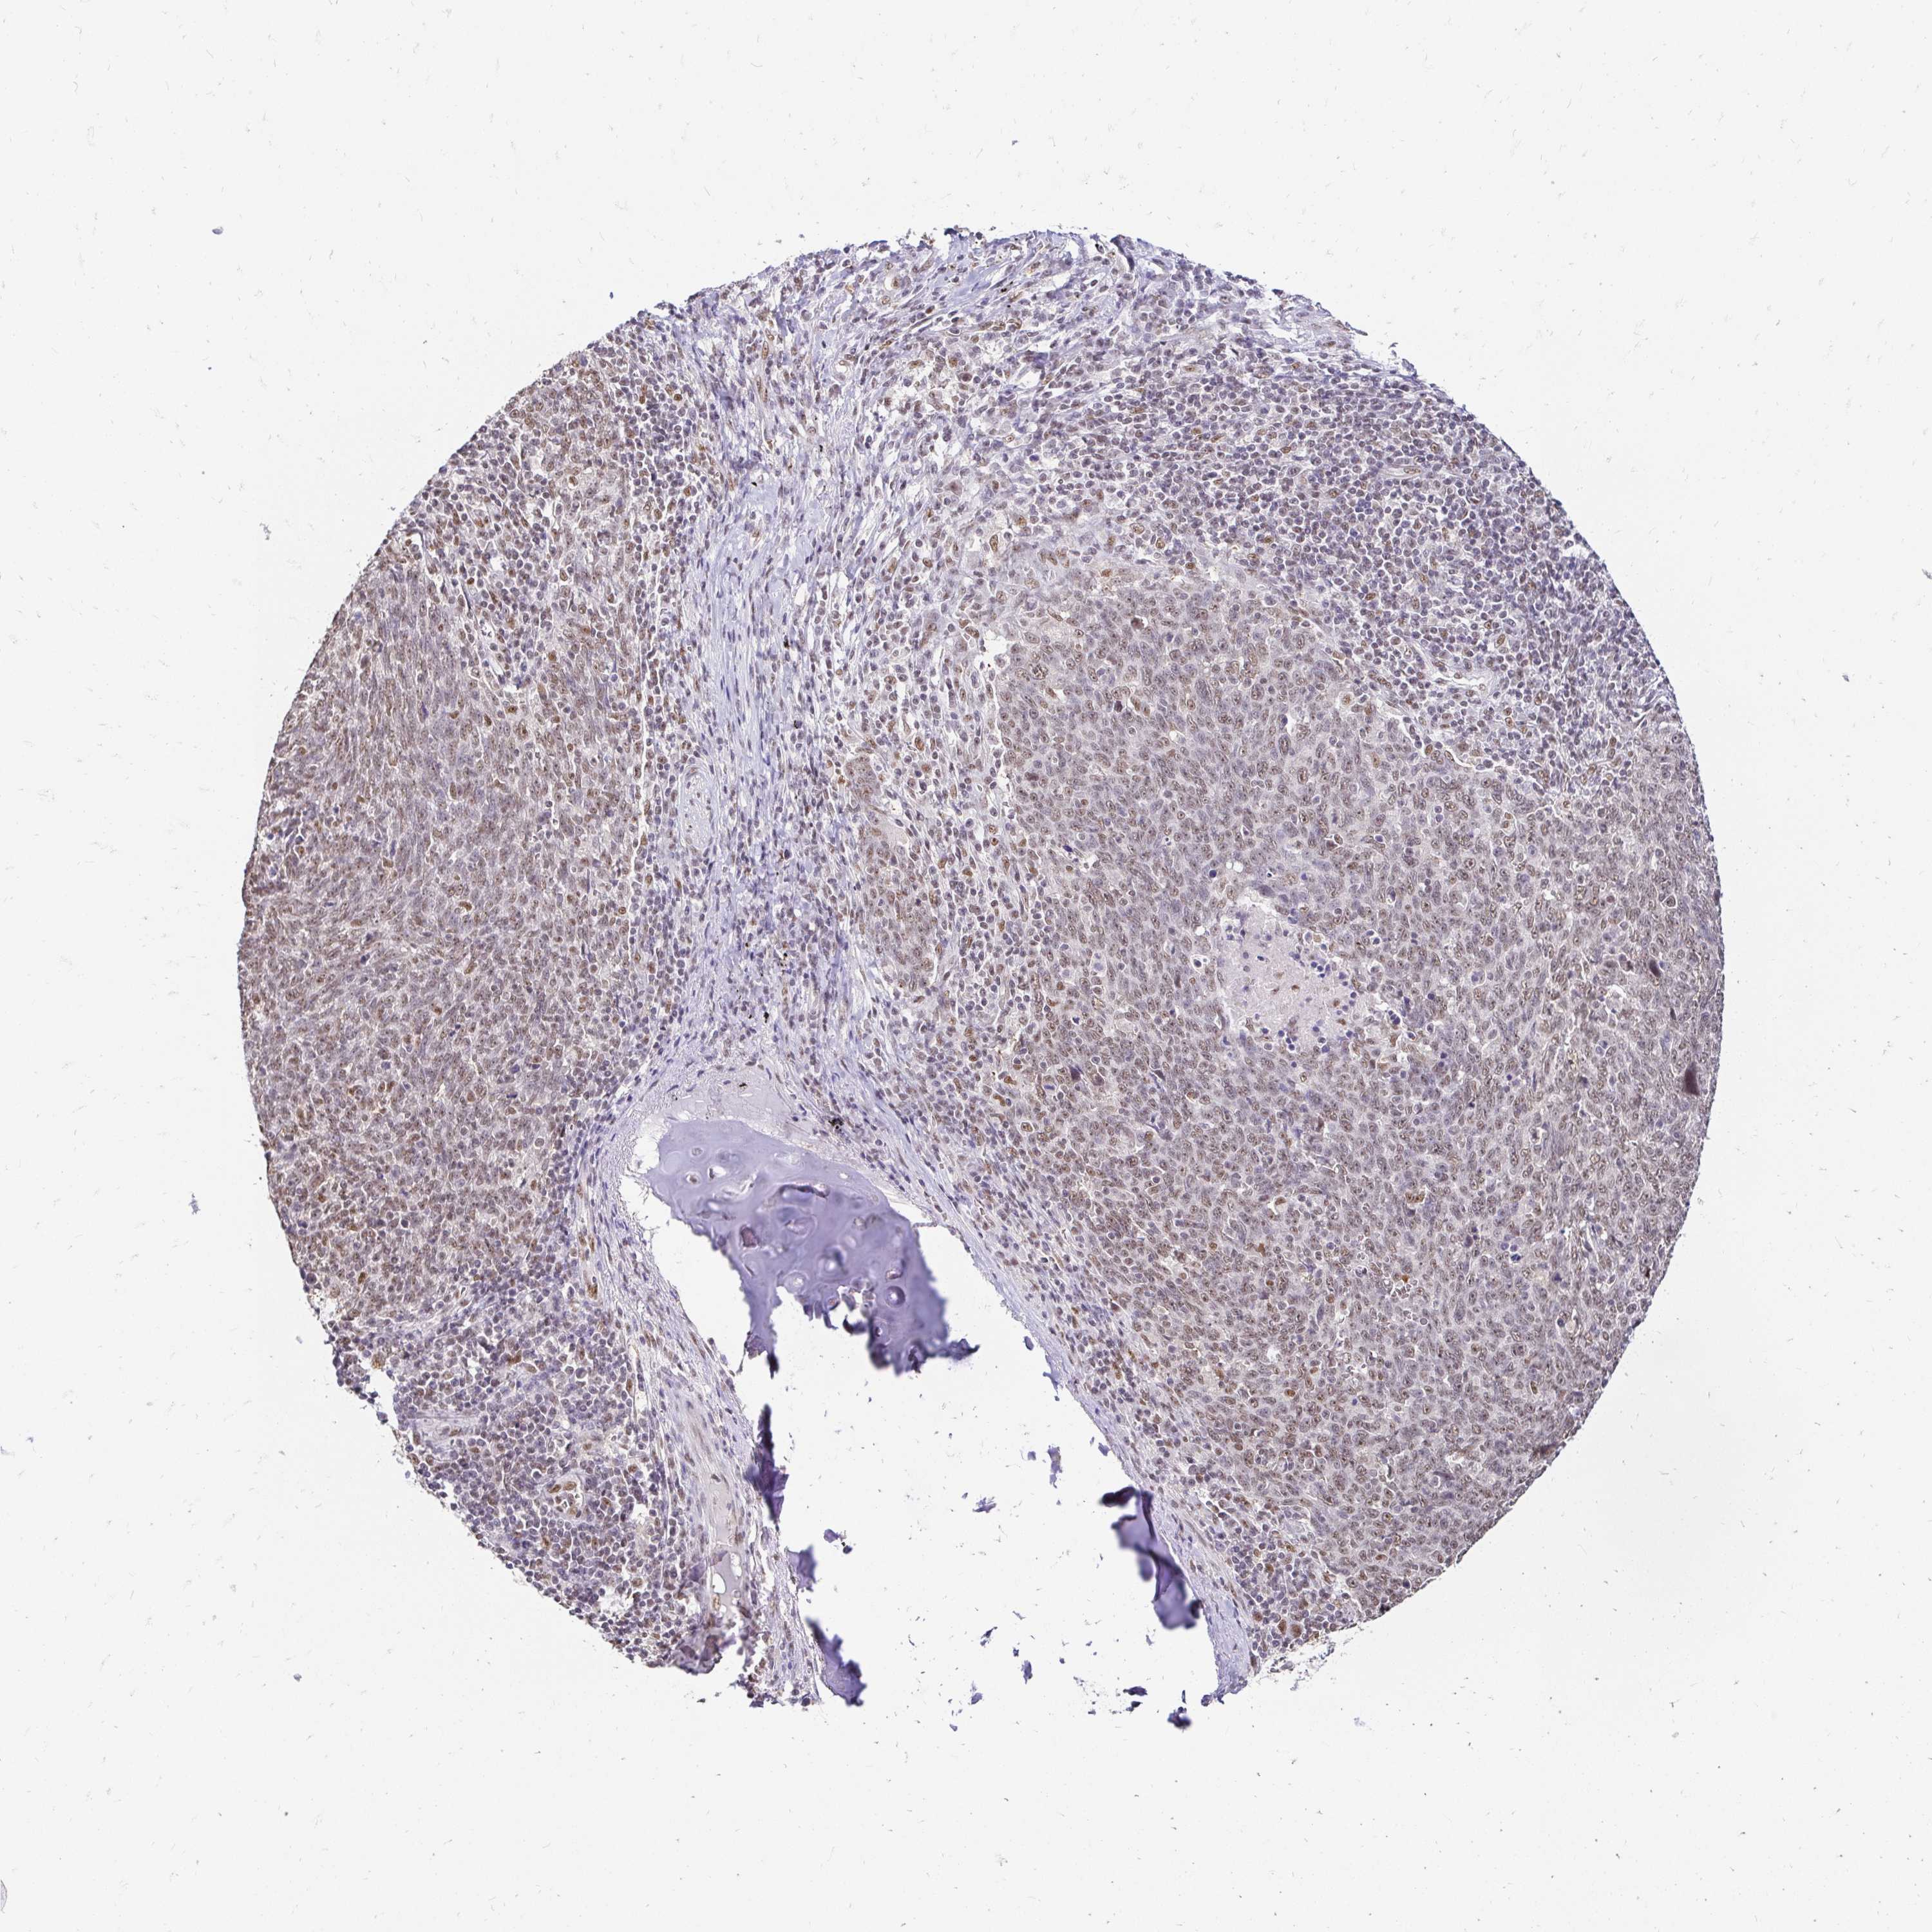

CANCER LUNG CANCER Show tissue menu

LUAD TCGA LUAD VALIDATION LUSC TCGA LUSC VALIDATION PROTEIN LUAD CPTAC PROTEIN LUSC CPTAC PROTEIN EXPRESSION